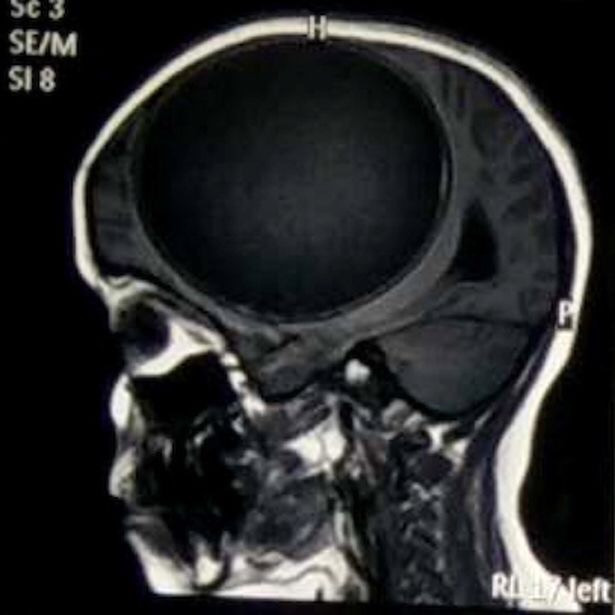

Nang sán dây "lớn nhất lịch sử y học" trong đầu cô bé 12 tuổi ảnh 1Ổ nang chiếm tới 1/2 bộ não. (Nguồn: mirror.co.uk)

Sau khi kiểm tra kỹ và chụp cộng hưởng từ, họ phát hiện một nang sán khổng lồ trong não cô bé.

Nang sán này nặng 675g, với kích thước 12,2x11x9,8cm.

Ổ nang sán này to bằng 1/2 kích thước bộ não, trông như một quả bóng căng phồng và rất nguy hiểm bởi khi vỡ, nó có thể khiến cô bé tử vong bất cứ lúc nào.